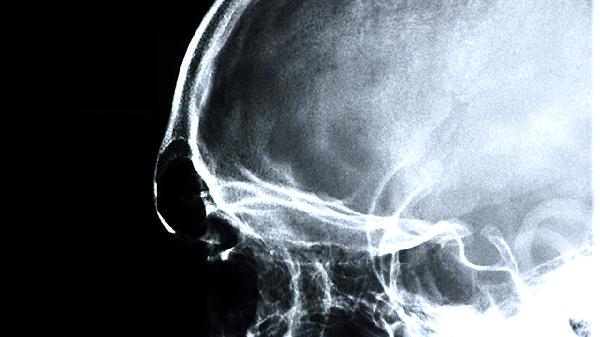

3、改善脑循环

清脑复神液能扩张脑部微血管,增加脑组织血氧供应,对动脉硬化或脑血管狭窄导致的头昏、记忆力减退有改善作用。老年患者使用时应监测血压变化,避免与降压药物产生协同作用而导致低血压。